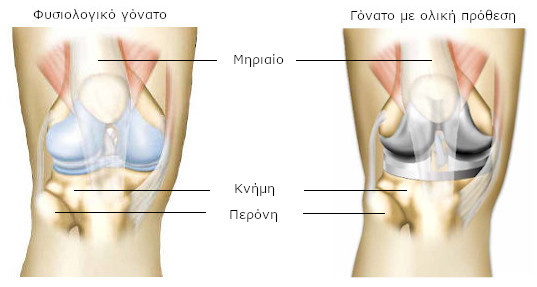

Άρθρωση είναι το σημείο όπου συνδέονται τα οστά μεταξύ τους, για να επιτρέπεται η κίνηση προς συγκεκριμένες κατευθύνσεις. Η άρθρωση του γόνατος επιτρέπει να λυγίζουμε και να τεντώνουμε το γόνατο όταν περπατάμε. Κατά τις κινήσεις αυτές, η κνήμη περιστρέφεται χωρίς να το συνειδητοποιούμε (αυτές οι κινήσεις ονομάζονται περιστροφικές).

Αυτή η άρθρωση στηρίζει το βάρος του σώματος και πρέπει να είναι σταθερή για να μην προκαλείται πτώση. Το γόνατο ενώνει το μηρό με την κνήμη.Το μηριαίο είναι το οστό του μηρού. Η κνήμη είναι το οστό που βρίσκεται κάτω από το γόνατο, στο μπροστινό μέρος του σκέλους, ενώ η περόνη βρίσκεται προς τα έξω και προς τα πίσω.

Καθώς το γόνατό σας έχει φθαρεί από αρθρίτιδα, η άρθρωσή σας έχει αντικατασταθεί από πρόθεση (πρόθεση γόνατος). Αποτελείται από ένα τμήμα τοποθετημένο στο μηριαίο και ένα δεύτερο στην κνήμη. Πρόκειται για ολική πρόθεση. Μερικές φορές υπάρχει και ένα τρίτο τεχνητό μέρος στο ύψος της επιγονατίδας (πρόθεση επιγονατίδας).

Τα τεχνητά μέρη της άρθρωσης είναι στερεωμένα στο οστό με ή χωρίς τη χρήση ειδικού τσιμέντου. Τα δύο μέρη της πρόθεσης ολισθαίνουν μεταξύ τους και αναπαράγουν τη φυσιολογική λειτουργία της άρθρωσης.